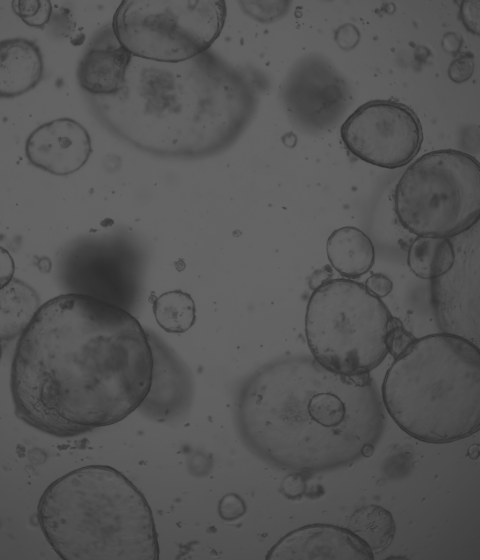

廈門模基生物科技有限公司致力于3D細胞培養(yǎng)核心原材料的研發(fā)與產業(yè)化升級,是國內一家從科研做起,從實驗研究中一路走來的全流程自主研發(fā)、自主生產的企業(yè)。目前公司的產品有基質膠、類器官培養(yǎng)基、細胞因子、3D細胞培養(yǎng)耗材、3D細胞培養(yǎng)智能顯微鏡等。公司擁有4大技術研發(fā)中心:分子克隆和細胞編輯中心、實驗動物中心、蛋白表達和純化平臺、類器官質檢系統(tǒng)和自動化。